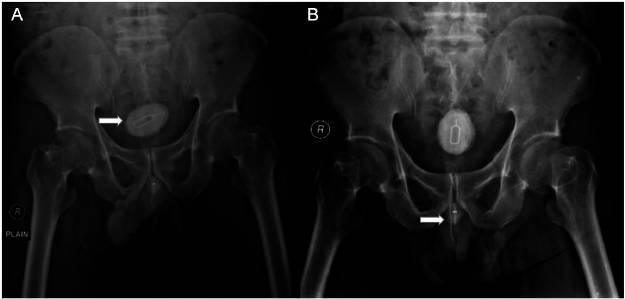

体格检查显示无耻骨上压痛、隆起或肿块。血液检查显示轻度贫血,血尿素氮升高为171 mg/dL(19.3-49.2 mg/dL),血肌酐升高为12.4 mg/dL,提示严重肾功能衰竭。尿液分析见白细胞和红细胞,提示尿路炎症。腹部X光片显示盆腔有一不透光异物及一个类似金属丝的线性不透光阴影(图1)。尿道造影显示充盈缺损和尿道扩张(图2)。CT扫描证实双侧肾积水和输尿管积水,以及大小为4.4×3cm的膀胱结石。大小为1.9×1.2cm的尿道结石也显著可见,并伴有类似金属丝的线性异物(图3)。CT扫描证实为梗阻性肾病。

图1 腹部平片显示盆腔内有一个5.5×3.7厘米的不透光阴影,以SIM卡插入器为核心,耻骨支水平处有一个1.9厘米高的细丝状不透光阴影